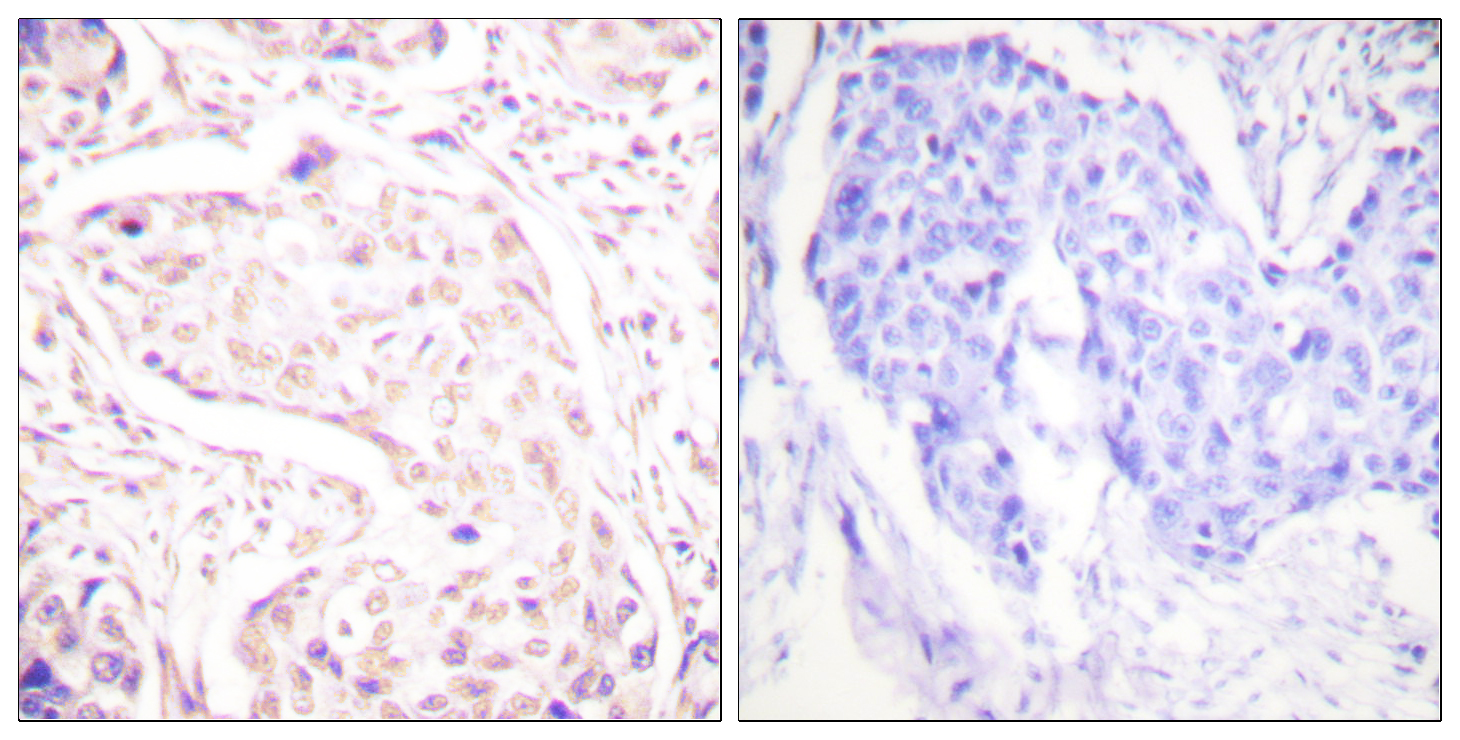

Anti-VHL AntibodyA98308

ApplicationsELISA, ImmunoHistoChemistry

ReactivityHuman, Mouse, Rat